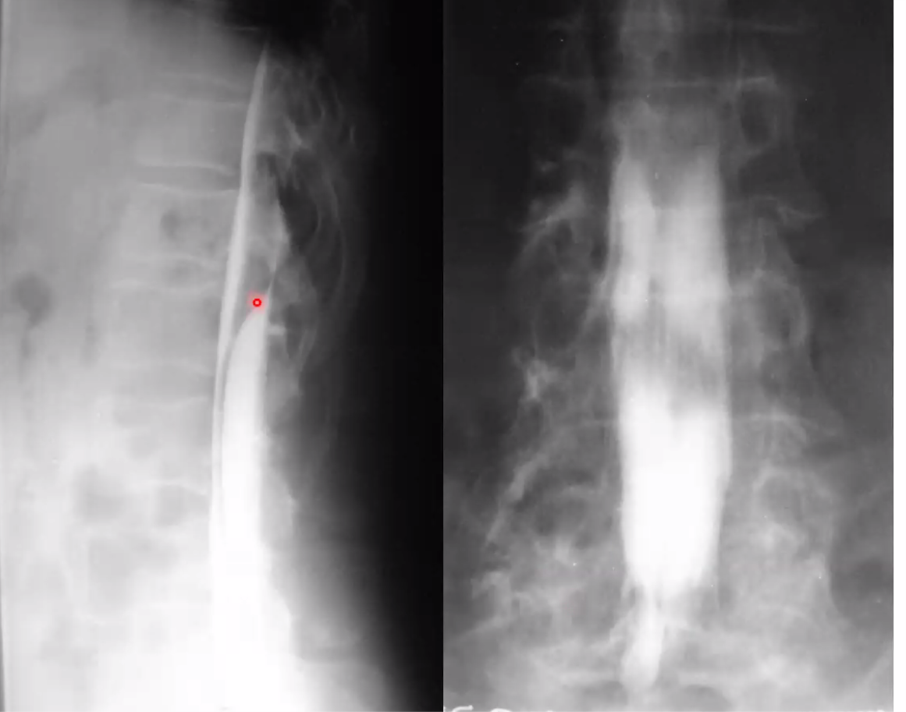

Spinal DAVF will have no flow voids in the cord itself, with have funky serpentine vessels surrounding the cord

spinal avm

notice the flow voids in the spiral cord. Spinal DAVF will have no flow voids in the cord itself, with have funky serpentine vessels surrounding the cord